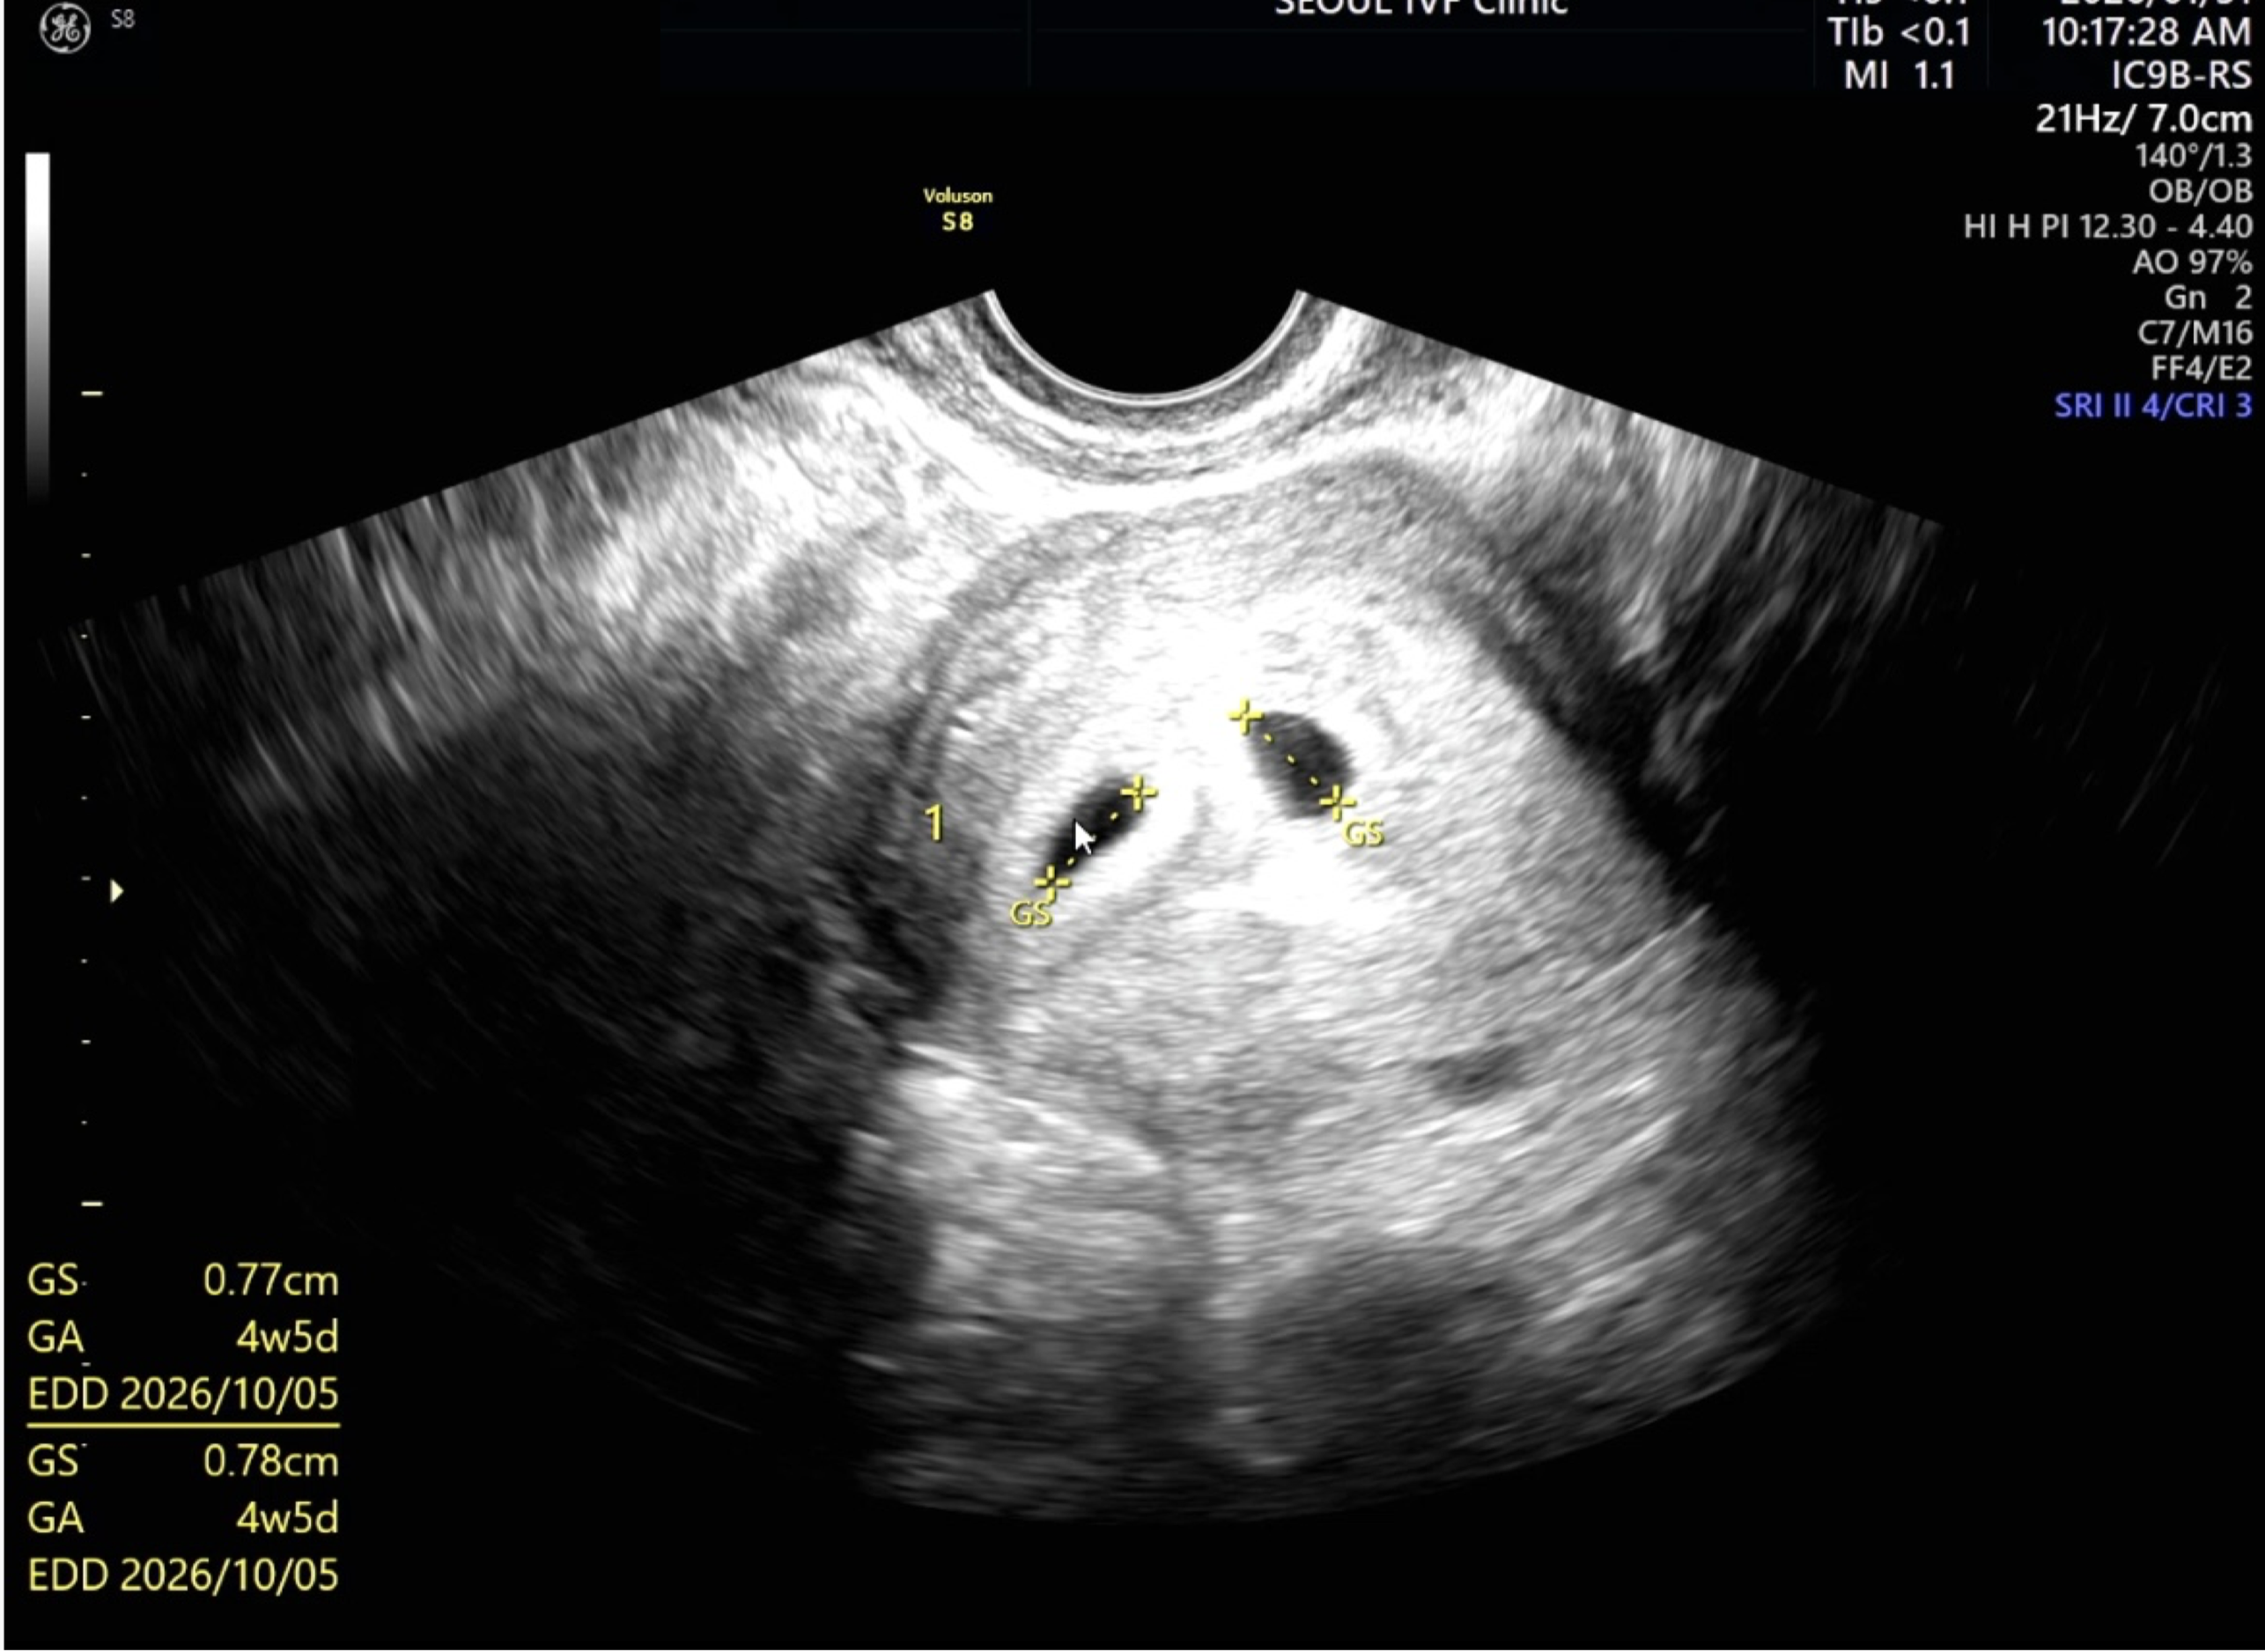

| 가슴 떨리는 임신 이야기를 공유해 주세요. | 평소 생리가 불규칙해 배란 초음파를 보며 1년 동안 자연임신을 시도했지만 임신이 되지 않아 난임병원을 찾게 되었습니다. 구월동 내 병원을 고민하던 중 후기가 좋아 서울아이비에프여성의원을 선택하게 되었습니다. 이전에도 난소에 혹이 보이긴 했었는데, 게속 지켜보자는 얘기만 들었었는데 이예흔 원장께서 이상 소견을 발견해 추가 확인을 진행해주신 덕분에 자궁내막증을 알게 되었습니다. 그 원인으로 임신이 어려웠던 것으로 판단되어 바로 시험관 시술을 진행하게 되었고, 첫 번째 시도 만에 임신에 성공해 쌍둥이를 만나게 되었습니다. 이예흔 선생님께서 항상 친절하게 맞이해주셨고, 시술과정도 의문없이 믿고 따를 수 있었습니다. 이예흔 원장님 그리고 간호 선생님들, 병원 모든 분들 너무 감사하고, 배아 연구원분들도 정말 감사합니다!! |

| 치료 도중 느꼈던 가장 기뻤던 순간과 절망적인 것들은 무엇인가요? 잊지 못할 경험이 있나요? | 난자 채취에서 14개가 나와 괜찮다고 생각했지만, 최종적으로 남은 배아가 3일 배아 2개뿐이었을 때 가장 걱정이 컸습니다. 하지만 그 2개의 배아로 쌍둥이를 만나게 되어 지금은 감사한 마음뿐입니다. |